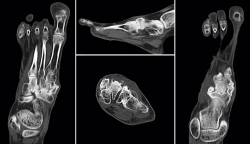

También se hizo un estudio gammagráfico (Figura 4) donde se aprecia un incremento de actividad en la fase vascular, en la fase tisular y en el estudio óseo tardío, lo que indica la presencia de componente inflamatorio añadido a la pseudoartrosis.

Figura 4. Gammagrafía.